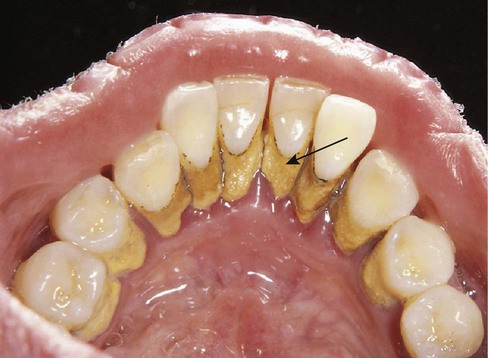

Calcium and phosphate salts in the saliva form calculus, which is commonly called “tartar.” Calculus is a hard, stonelike material that attaches to the tooth surface. The surface of calculus is porous and rough and provides an excellent surface on which additional plaque can grow. Calculus can penetrate into the cementum on root surfaces. It cannot be removed by the patient and must be removed by the dentist or the dental hygienist with the use of scaling instruments. Regular, effective plaque control measures can minimize or eliminate the buildup of calculus. Plaque control measures are discussed in Chapter 15.

Calculus is usually divided into supragingival and subgingival types, even though these types often occur together.

Supragingival calculus is found on the clinical crowns of the teeth, above the margin of the gingiva. It is readily visible as a yellowish-white deposit that may darken over time (Fig. 14-3).

Supragingival calculus occurs frequently near the openings of Wharton's ducts (on the lingual surfaces of the lower anterior teeth) and Stensen's ducts (on the buccal surfaces of the maxillary molars).